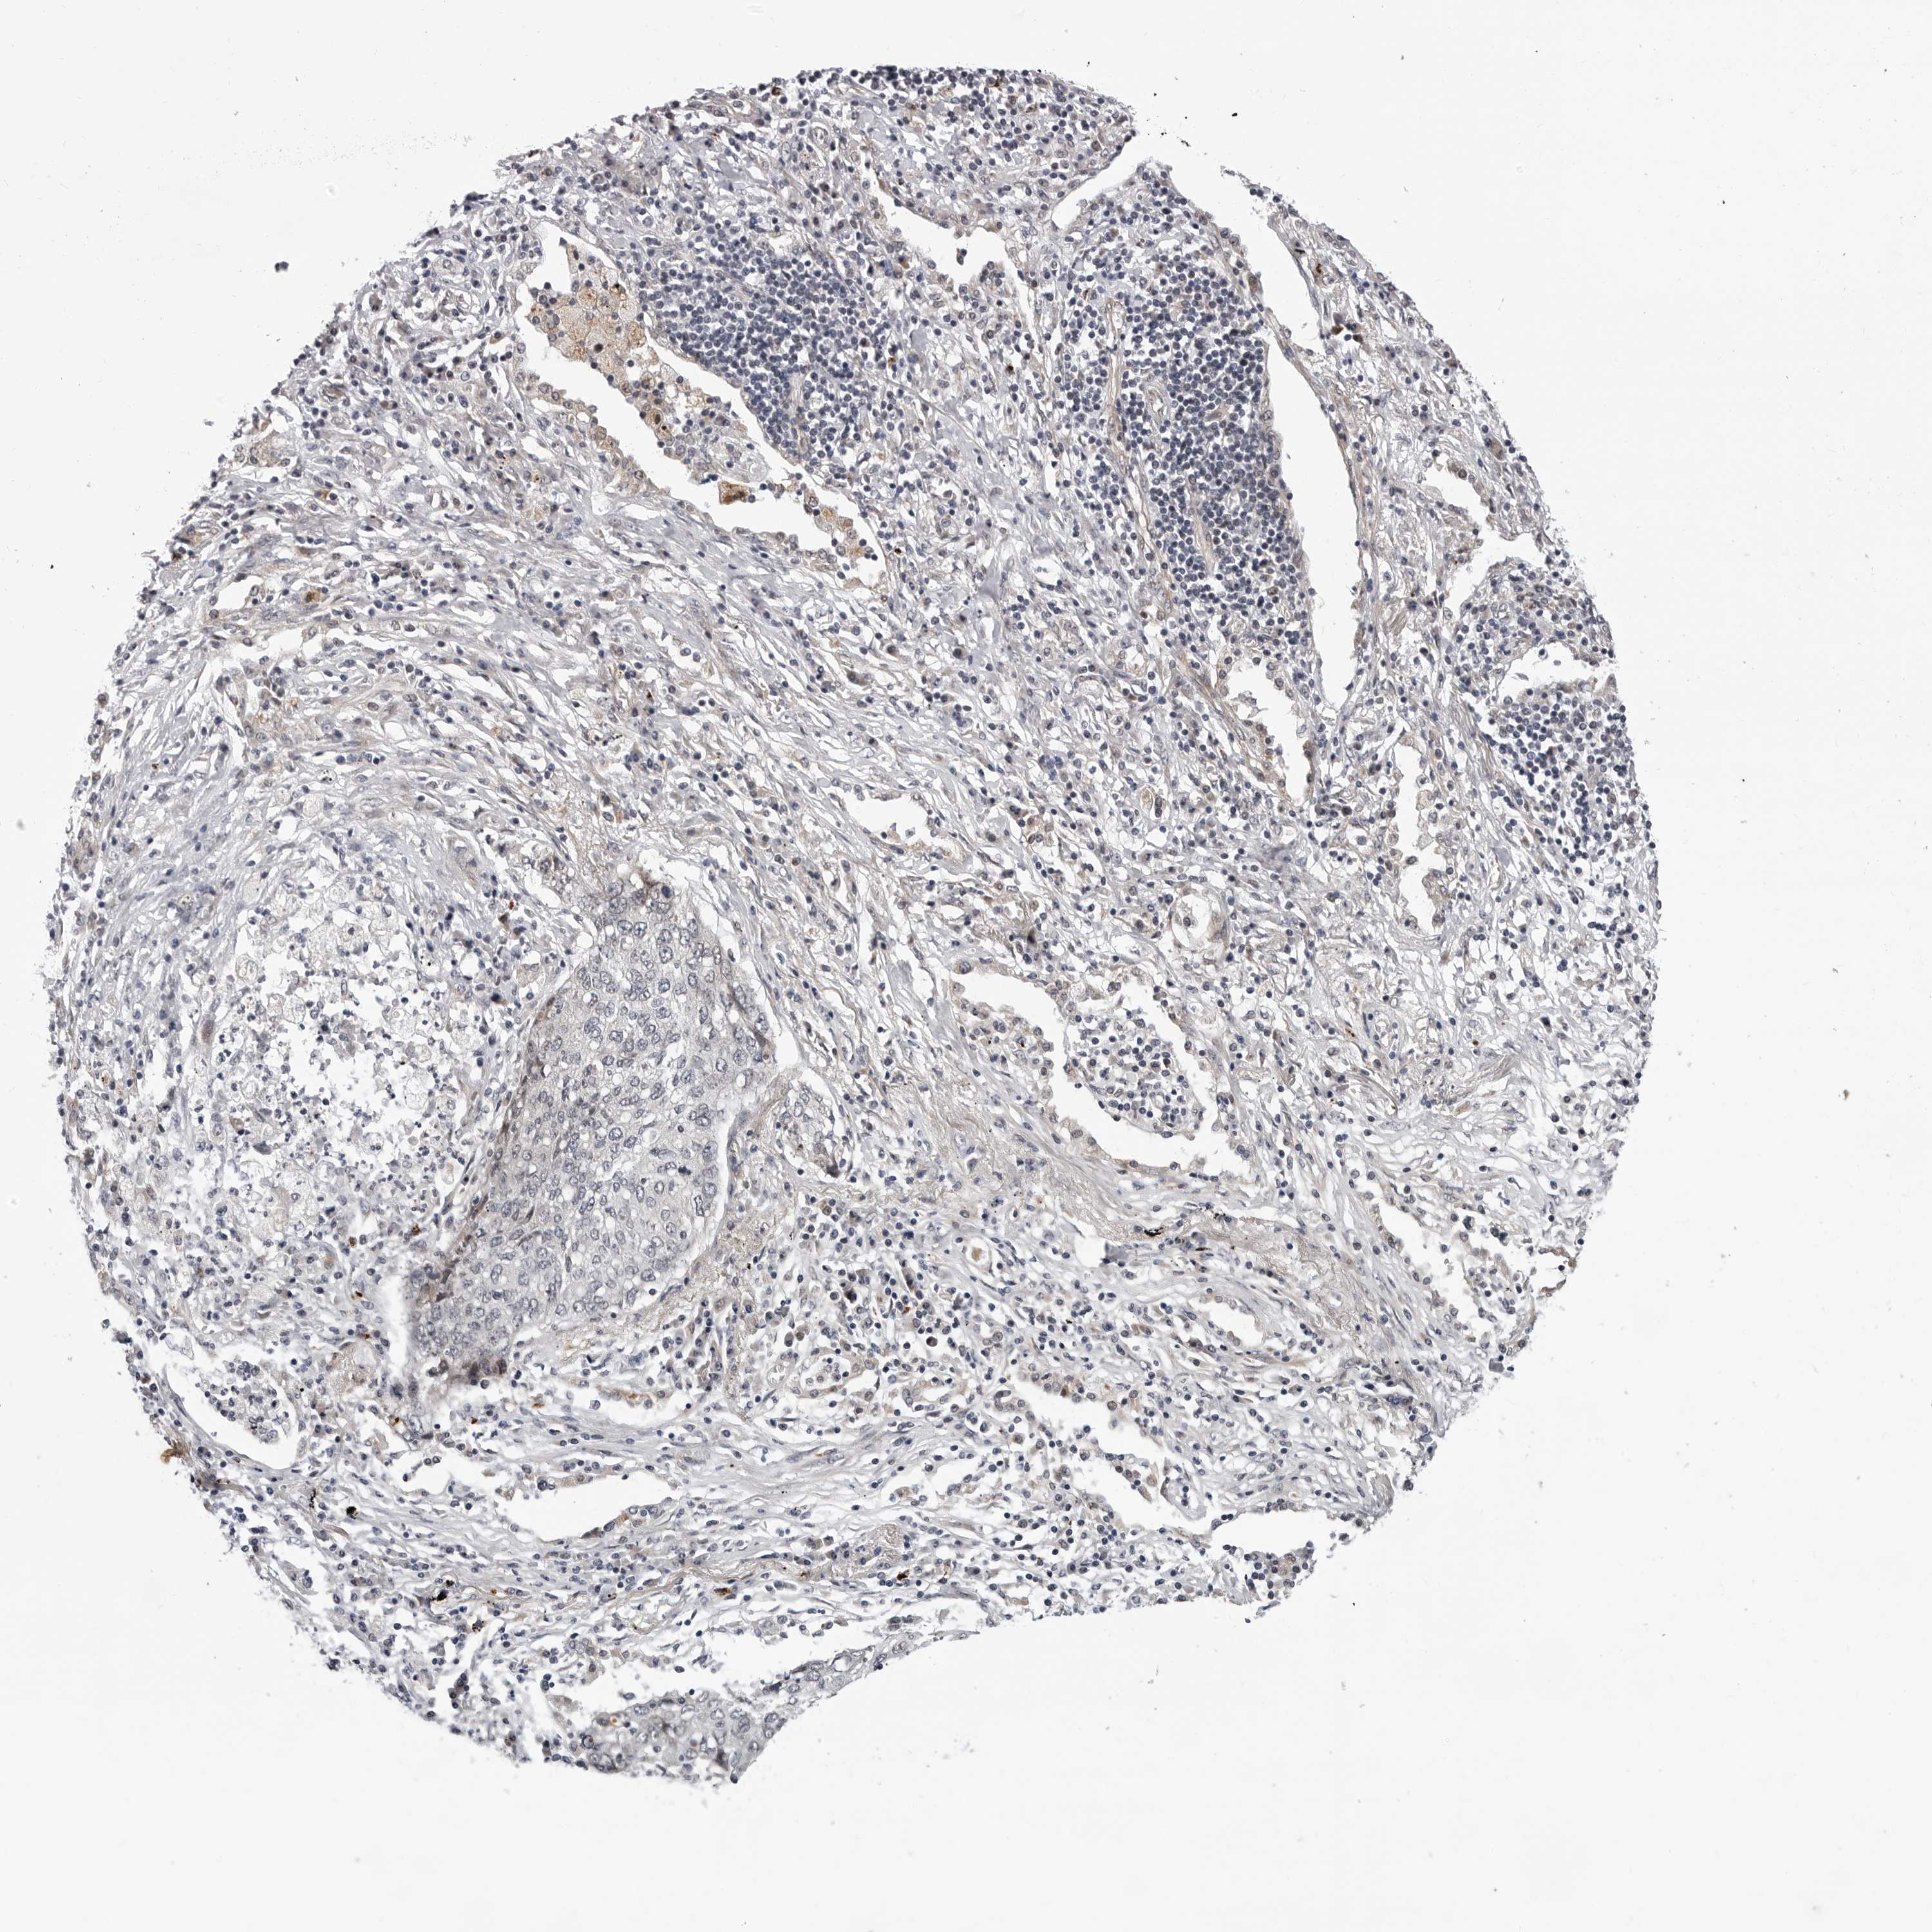

CANCER LUNG CANCER Show tissue menu

Lung cancer

Human cancer

Lung adenocarcinoma

Lung squamous cell carcinoma